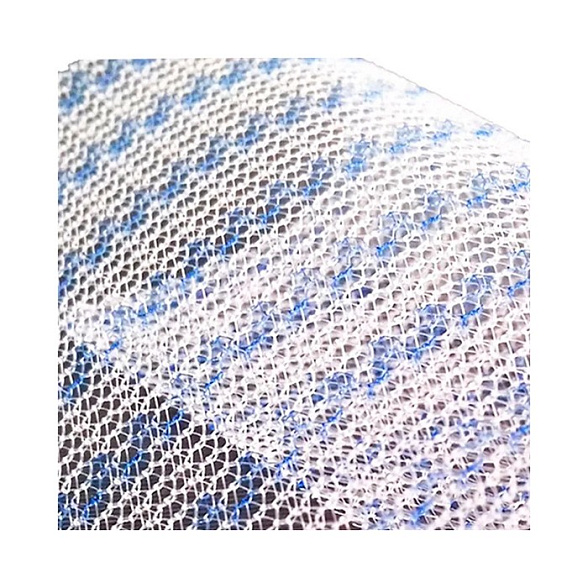

- Оптимальная интеграция с тканями: Особое плетение и структура материала способствуют активному прорастанию соединительной ткани (фиброзной и коллагеновой), обеспечивая надежную фиксацию импланта и формирование единого анатомического комплекса.

- Лёгкость и эластичность: «Лёгкая» модификация сетки обладает сниженной плотностью и массой, что минимизирует ощущение инородного тела у пациента после операции и повышает комфорт в отдаленном периоде.

| Структура | Макропористая, неабсорбируемая (нерассасывающаяся) |